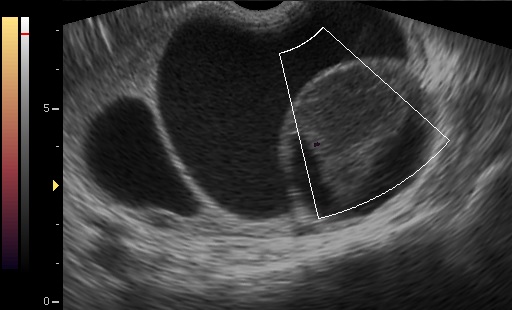

Ultrasound characteristics of adnexal torsion include:

- Presence of ovarian cyst/tumor, or parovarian cyst or hydrosalpinx (usually as a prerequisite).

- Edematous ovary and/or tube with increased intrafollicular distance and/or follicular halos.

- Abnormal or absent doppler flow inside the ovary.

- The whirlpool sign.